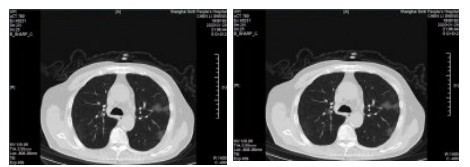

| 图 2 患者,女性,64岁,武汉籍,发病前1 d由武汉自驾车入沪,出现发热,体温39.9℃, 伴全身乏力,无咳嗽症状,无鼻塞,流涕症状,血白细胞总数及淋巴计数正常,甲乙型流感病毒筛查阴性,新型冠状病毒核酸检测阳性,肺部CT双肺多发磨玻璃结节,部分贴近胸膜,左肺有少量胸腔积液,局部小叶间隔增厚, 可见纤维条索影 Fig 2 Case 2, female, 64 years old, born in Wuhan. One day before the onset of the disease, she drove into Shanghai from Wuhan and had fever. Her body temperature was 39.9℃, with general asthenia, no cough, no nasal obstruction and running nose, normal WBC and lymphoid count, negative influenza A and B virus screening, positive novel coronavirus nucleic acid test. Lung CT showed multiple ground glass nodules, some of which were close to pleura, a small amount of pleural effusion in the left lung, and local interlobular septa was thickened, with visible fibrous streak shadow |

| 图 3 患者,女性,49岁,沪籍,发热10 d,体温最高38.5℃,伴乏力,肌肉酸痛,既往体健。否认武汉流行病学接触史,有菜场买菜史。血白细胞总数及淋巴计数正常,甲型、乙型流感筛查阴性,新型冠状病毒核酸检测阳性。肺部CT提示双肺磨玻璃结节,可见血管充血,增粗,穿行,部分贴近胸膜,伴小叶间隔增厚 Fig 3 Case 3, female, 49 years old, born in Shanghai, had fever for 10 days, body temperature 38.5℃, with fatigue, muscle pain, previous physical fitness. She denied the history of epidemic exposure of Wuhan, but had the history of shopping in market. Normal WBC and lymphoid count, negative influenza A and B virus screening, positive novel coronavirus nucleic acid test. Lung CT showed bilateral ground glass nodules with hyperemia, thickening and passage of blood vessels. Some were close to pleura with thickening of interlobular septum |